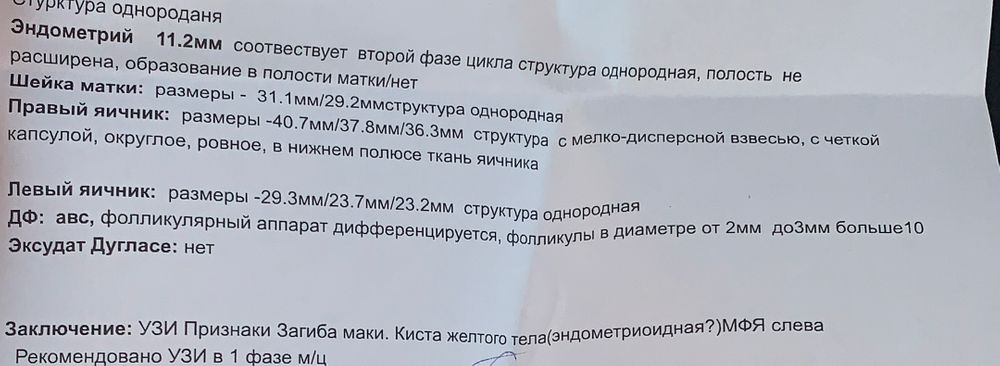

Киста желтого тела(эндометриодная?)

Здравствуйте . Кто сталкивался? Напугали кистой. До этого была киста ЖТ два цикла и исчезала после месячных. А теперь ставят другую под вопросом

Эндометриоидная за раз до таких размеров не вырастет. Они бывают похожи с кистой ЖТ, обычно еще кровоток смотрят. В любом случае узи в динамике, и будет понятно.